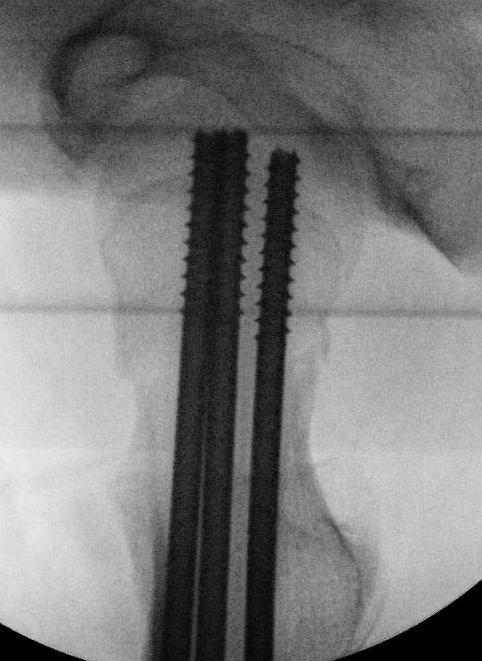

Fixation

- < 3 years K wires crossing physis

- > 3 cannulated screws crossing physis

Spica post op < 10 years